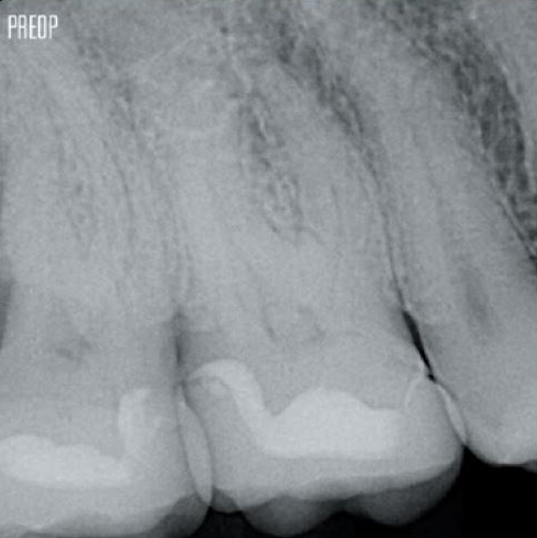

Photos courtesy of Dr. Ahmed Salman

More dentin preserved. Appropiate shaping, irrigation, and obturation ensured.

Successful root canal treatment starts with adequate access to the pulp chamber. The ideal procedure provides access to root canal orifices with minimal loss of dentin.

A Conservative Endodontic Cavity (CEC) is the recommended with the TruNatomy® system.

The union of the file geometry, regressive tapers and the slim, highly-flexible wire enables efficient root canal treatment while removing only dentin where clinically needed.1